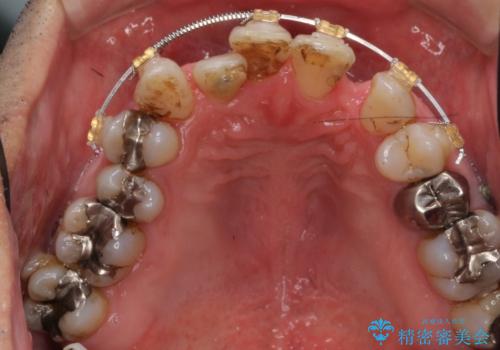

前歯の部分矯正を行い受け口を改善しました。

奥歯まで動かそうとすると顎の手術の適応になってしまうため、奥歯はそのままにして前歯のかみ合わせを改善しました。

また、奥歯はインプラント治療を行い、矯正で下の前歯を後ろに下げるのに使用しています。

前歯が重なっているところの虫歯治療が難しく、そこから矯正治療の提案となりました。

下の前歯1本、また、左上2番を保存不可能なため抜歯しています。

通常骨格的な受け口を部分矯正でというのは不可能なことが多いのですが、今回はいろいろな条件が重ねなりお引き受け可能でした。通常は難しいです。